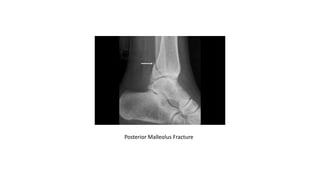

TYPES OF ANKLE FRACTURE & DISLOCATION

• POSTERIOR MALLEOLUS FRACTURE:

• is a fracture of the back of the tibia at the level of the ankle joint.

• In most cases of posterior malleolus fracture, the lateral malleolus (fibula) is also broken. This is because it shares ligament

attachments with the posterior malleolus. There can also be a fracture of the medial malleolus.

• Depending on how large the broken piece is, the back of the ankle may be unstable. Some studies have shown that if the

piece is bigger than 25% of the ankle joint, the ankle becomes unstable and should be treated with surgery.

• It is important for a posterior malleolus fracture to be diagnosed and treated properly because of the risk for developing

arthritis. The back of the tibia where the bone breaks is covered with cartilage. Cartilage is the smooth surface that lines a

joint. If the broken piece of bone is larger than about 25% of your ankle, and is out of place more than a couple of

millimeters, the cartilage surface will not heal properly and the surface of the joint will not be smooth. This uneven surface

typically leads to increased and uneven pressure on the joint surface, which leads to cartilage damage and the development

of arthritis.

Posterior Malleolus Fracture